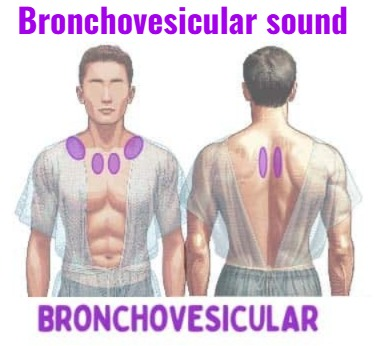

Bronchovesicular sound (બ્રોન્કો-વેસિક્યુલર સાઉન્ડ):

- બ્રોન્કો-વેસિક્યુલર એ નોર્મલ મીડીયમ પીચ સાઉન્ડ છે જેમાં ઇન્સ્પાયરેટરી અને એક્સપાયરી ટાઈમ સરખો જોવા મળે છે.